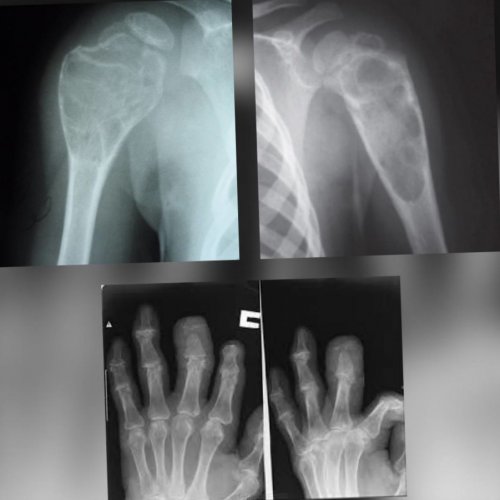

Диагностика